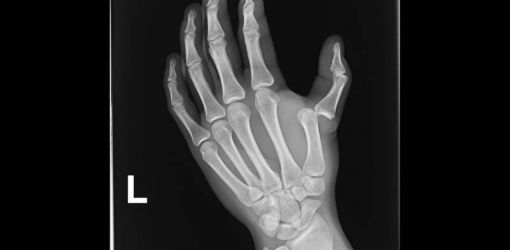

О случившимся женщина ни в милицию, ни водителю не сообщила. Примерно через два часа она обратилась в травмпункт больницы скорой медпомощи. Травматолог поставил диагноз – перелом пальца левой кисти. После оказания медицинской помощи гомельчанку отпустили домой.

Фото из Интернет-ресурсов